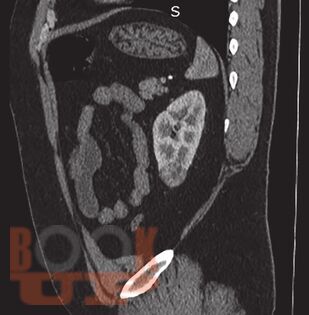

В данном учебном пособии представлены сведения по анатомии и физиологии почек, эпидемиологии, этиологии, патогенезу, клинике, диагностике и современному хирургическому лапароскопическому лечению опухолей почек.